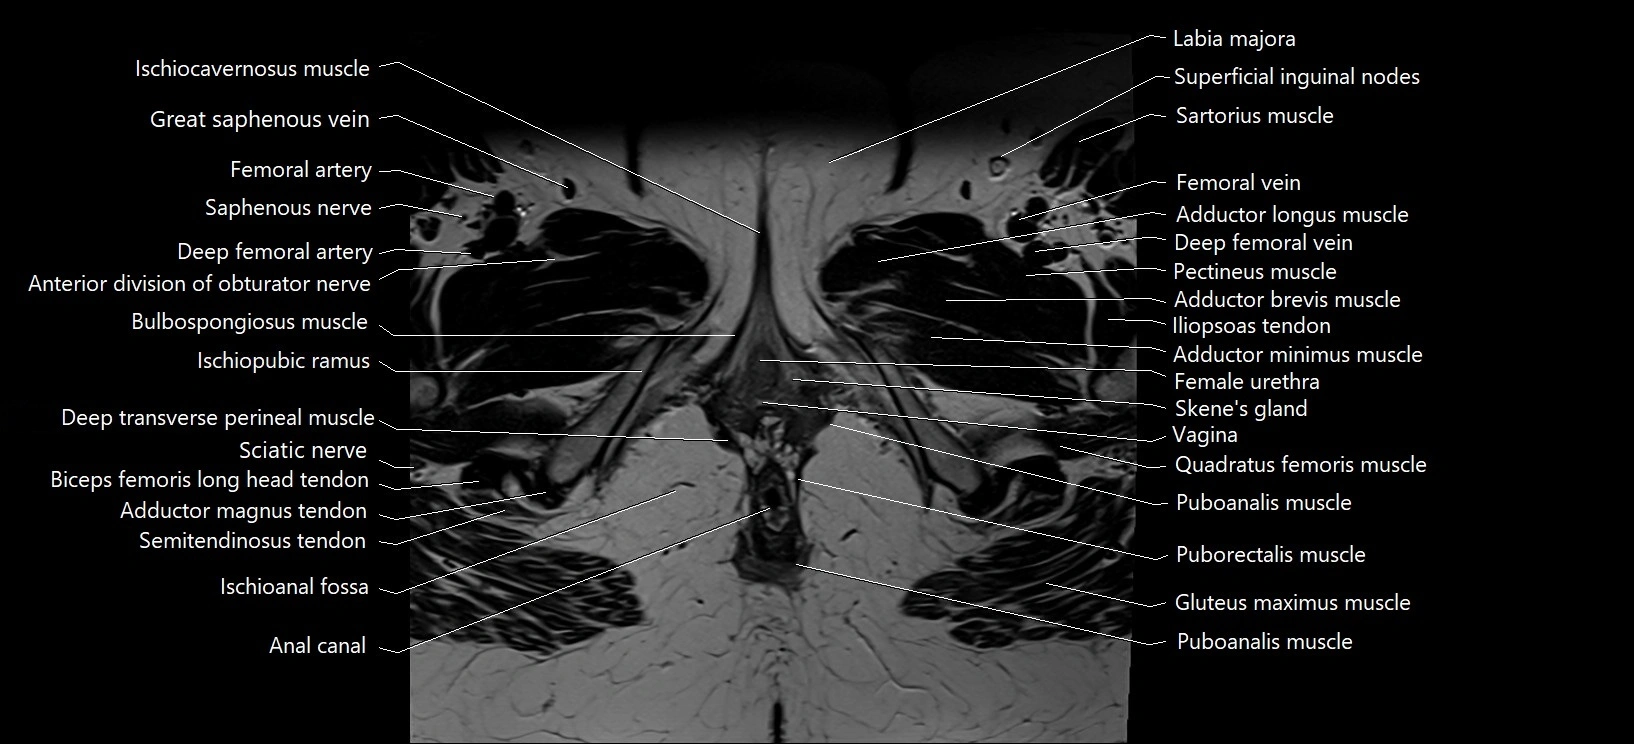

- Adductor brevis muscle

- Adductor longus muscle

- Adductor magnus muscle

- Adductor minimus muscle

- Anal canal

- Anterior division of obturator nerve (Anterior branch of obturator nerve)

- Bulbospongiosus muscle (Female)

- Deep femoral artery (profunda femoris)

- Deep femoral vein (profunda femoris vein)

- Deep transverse perineal muscle

- Female urethra

- Femoral artery

- Femoral vein

- Gracilis muscle

- Ischioanal fossa

- Ischiocavernosus muscle (Female)

- Ischiopubic ramus

- Labia majora

- Pectineus muscle

- Puboanalis muscle

- Puborectalis muscle

- Quadratus femoris muscle

- Saphenous nerve

- Sartorius muscle

- Sciatic nerve

- Skene’s gland (paraurethral glands)

- Superficial inguinal lymph nodes

- Vagina

- great saphenous vein